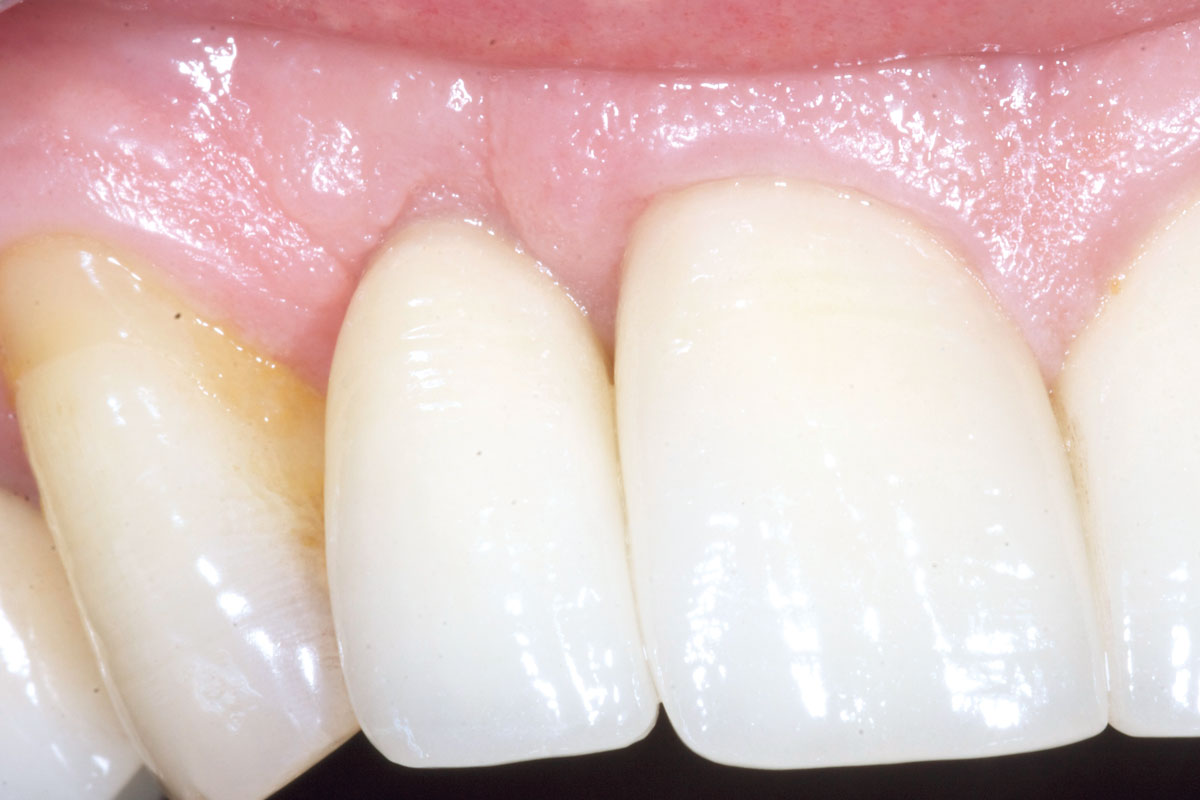

6/19 - Site without prosthetics showing sever buccal bone lossBone augementation with maxresorb® - Dr. R. Cutts